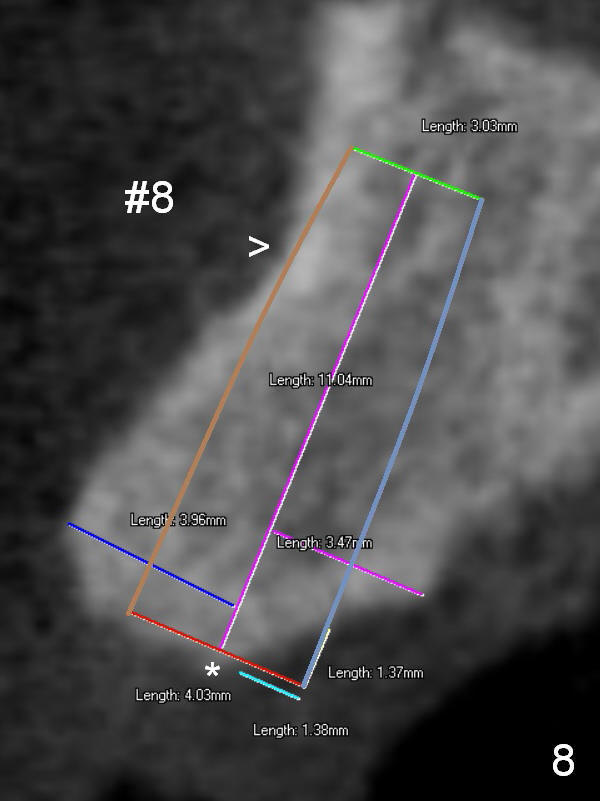

For the best trajectory, osteotomy at #8 should be initiated as palatally as possible (Fig.8 *). When a 4x11 mm 2-piece implant is placed, there is possibility that the apical buccal plate may be perforated (>). In contrast, a 3x11 mm 1-piece implant is more skinny with less coronal palatal thread exposure (Fig.9). The latter will be covered with bone graft and collagen dressing.

The second design is to place relatively smaller implants with the occlusion in mind (Fig.3,4). The starting point for the osteotomy will be as lingual as possible (especially Fig.4). The axis of the implant will be more parallel to the buccal plate. The angles of the angled abutments will be less (Fig.1 vs. 3; Fig.2 vs. 4). The cosmetic result may be better.